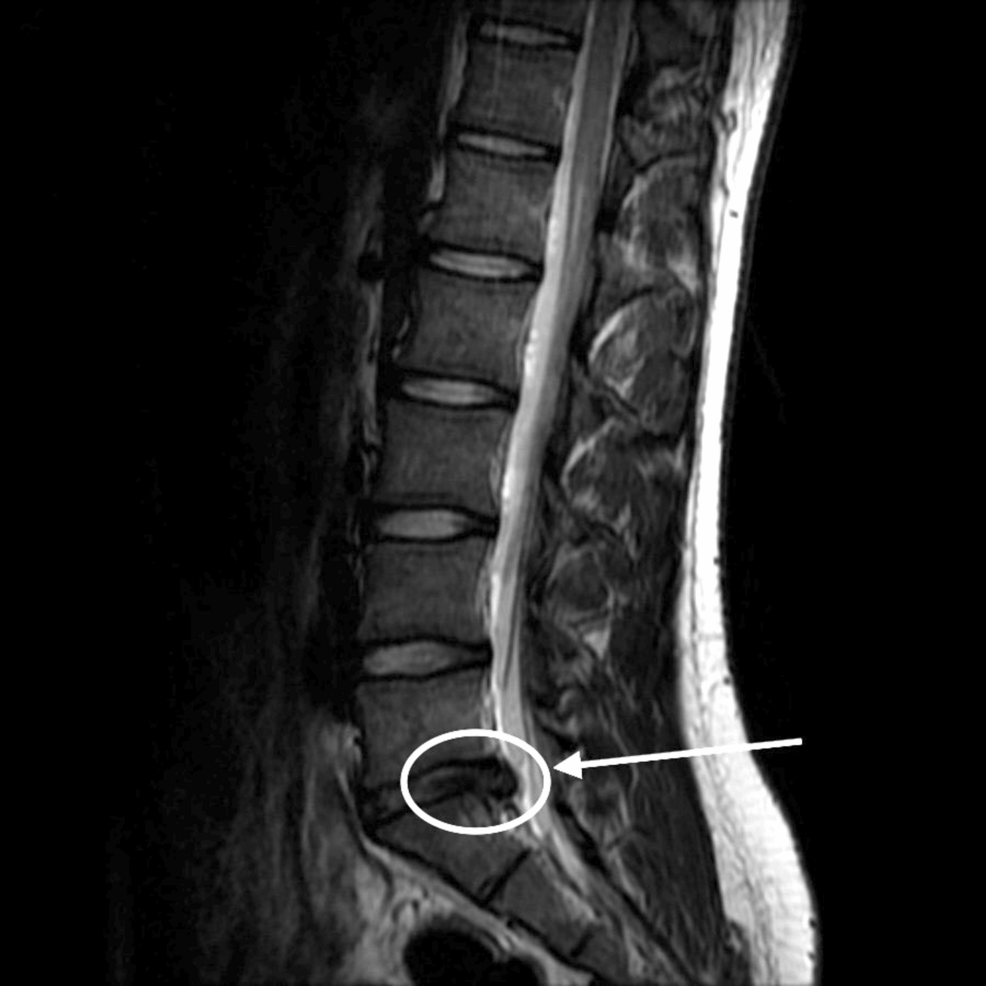

Diagnostic images show new disc problems or swelling that started after the crash. The doctor reports tracking your condition from day one. Your pain journal captures the daily reality that no scan can.

When your case moves to settlement talks or court, these records become key evidence. They help calculate medical costs, lost wages, and fair payment for pain and suffering. Notes from a specialized clinic, such as El Paso Back Clinic, hold significant value because of their focus on soft-tissue injuries commonly encountered in accidents.